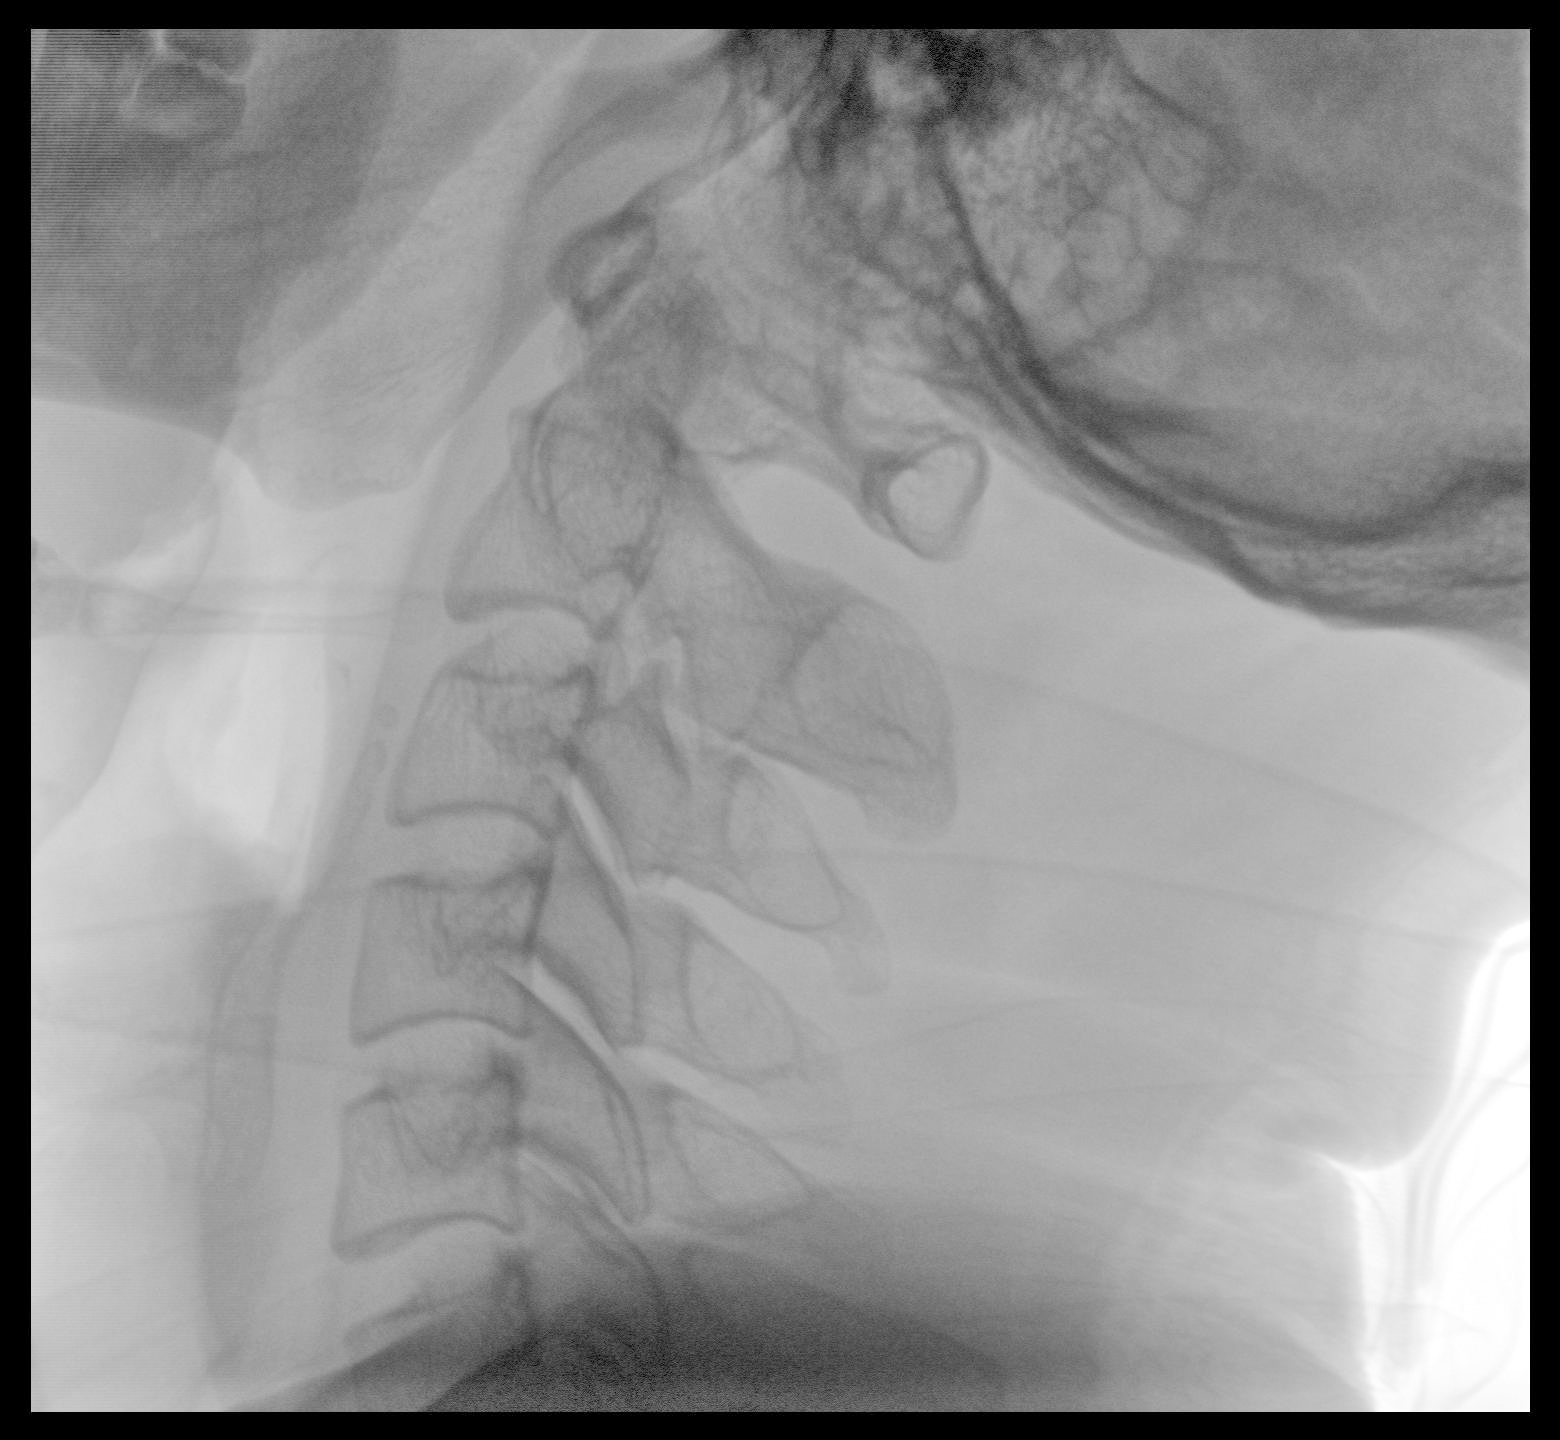

PLX118F-Plus配備了兩種平板尺寸,大尺寸動(dòng)態(tài)平板探測器成像面積較傳統(tǒng)平板探測器提升了25%以上,在視野需求大的手術(shù)中,便于醫(yī)生更好定位病灶點(diǎn),規(guī)劃手術(shù)方案,減少因視野范圍不足而多次透視、點(diǎn)片造成的不便。